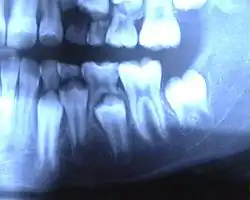

![]() Ротовая полость ребёнка семи лет: слева — молочный зуб, в центре — лунка выпавшего молочного зуба, справа — постоянный зуб. | |

Смена зубов

Период сохранения молочных зубов и прорезывания постоянных называют периодом сменного прикуса — после выпадения молочного зуба до прорезывания постоянного обычно проходит 3-4 месяца. В дальнейшем последовательность смены зубов примерно соответствует прорезыванию молочных зубов. В возрасте 11 лет прорезываются вторые моляры. К 12-13 годам формируется постоянный прикус. Третьи моляры (зубы мудрости) прорезываются в возрасте 17—25 лет или позже либо вообще не прорезываются. У девочек прорезывание зубов происходит несколько раньше, чем у мальчиков.